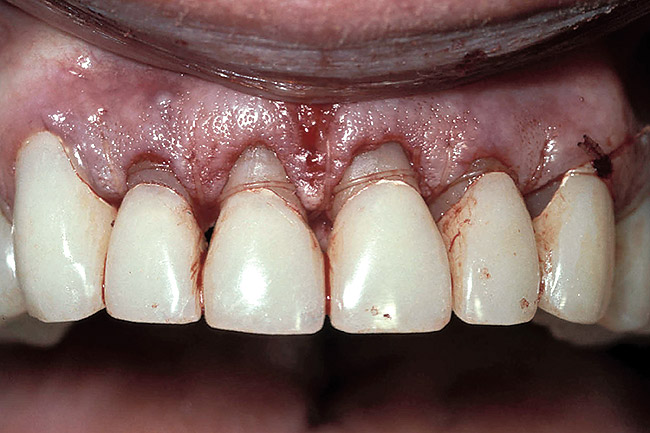

Figure 8  Osseous crown lengthening was performed using the incisal edge position of the temporary to determine bone and gingival levels.

Figure 8

Figure 9  View at 10 weeks post-surgery showing the new gingival level. The preparation and temporary will now be extended to the gingival level.

Figure 9